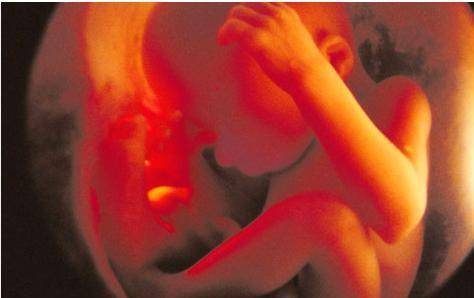

怀孕五个月,胎儿的发育

胎儿重约280克,长度超过15.24厘米。你的子宫应该在肚脐的水平位置。宝宝可以吮拇指,打哈欠,伸展,做鬼脸。很快, 如果你还没有,你会感觉到你的宝宝在移动,这被称为“胎动”。通常在20周时对所有孕妇进行超声检查,也就是大排畸。在超声检查期间,医生会确保胎盘健康并正常连接,并确保宝宝正常生长。您可以在超声波上看到胎儿的心跳以及身体,手臂和腿部的运动。